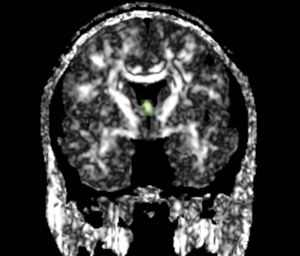

We apply fiber tractography to quantify fornix Fractional Anisotropy (FA) in schizophrenia. Two ROI method (shown in the figures) were used to extract left and right fornix in 34 chronic schizophrenia subjects and 40 matched controls, and mean FA along the entire tract was extracted separately for the left and the right sides and compared between groups. Preliminary data indicate bilateral decreased FA in the fornix of schizophrenics.

ROIs for Tractography

Fornix roi1.jpg Fornix roi2.jpg